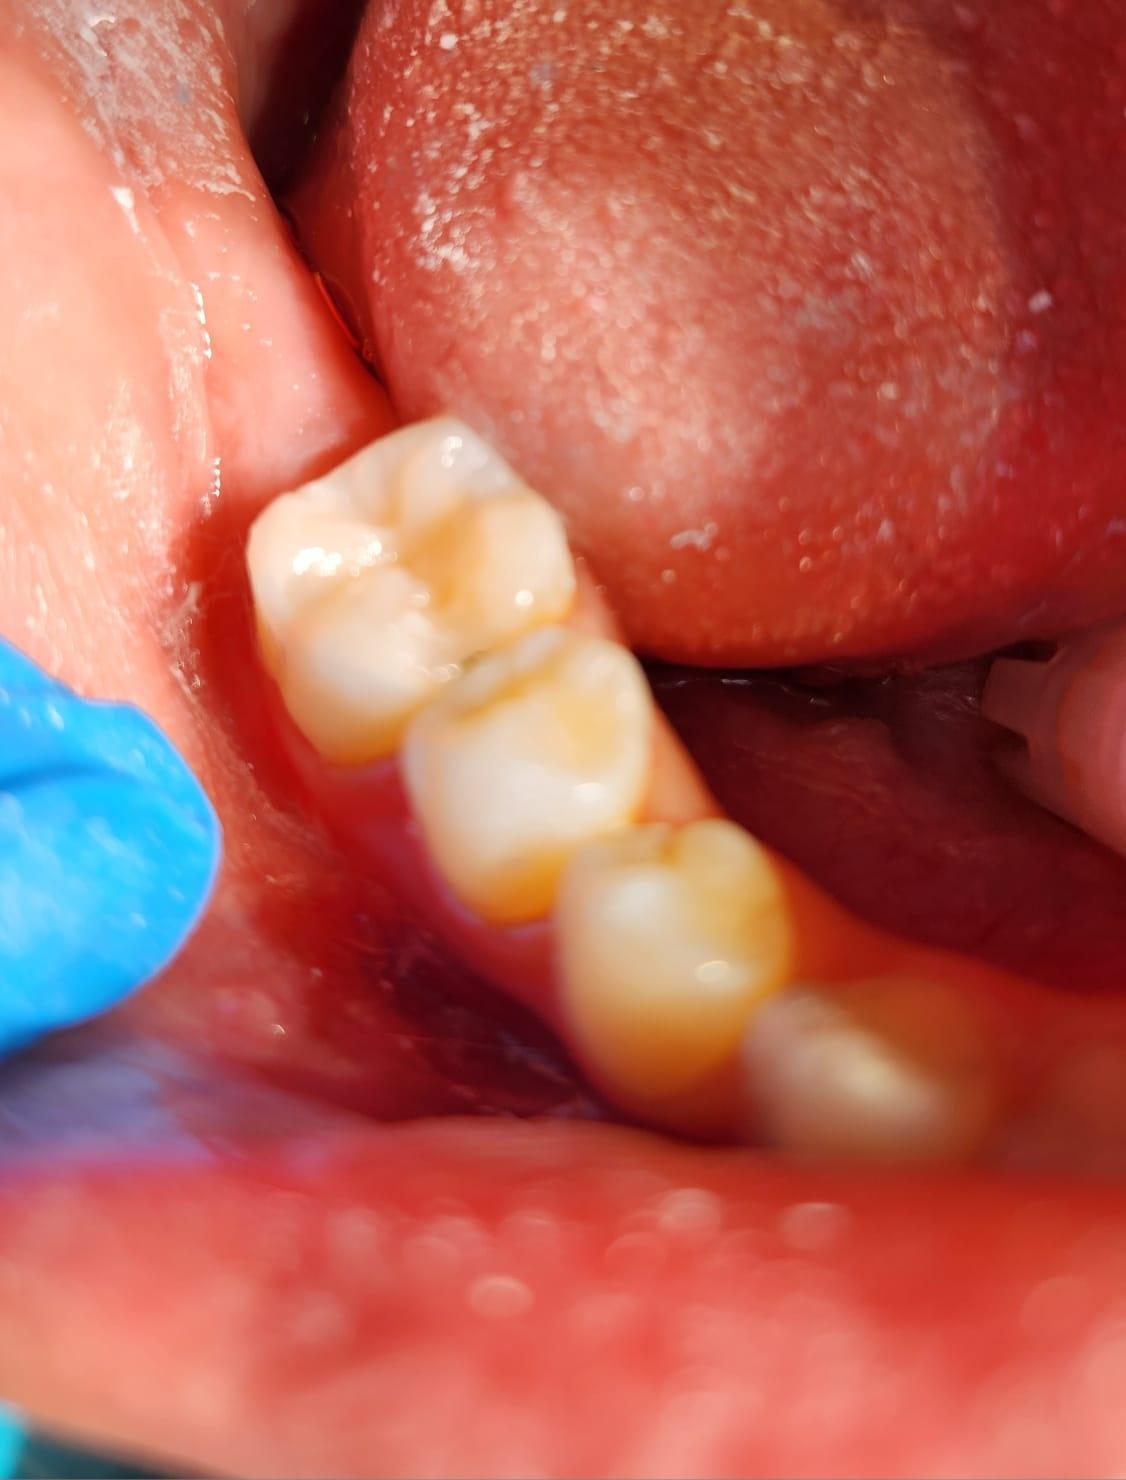

– mobilitatea sau deplasarea dintilor;

– retractii gingivale cu expunerea radacinilor dentare;